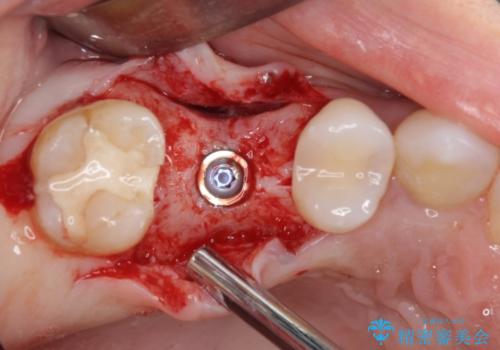

診察の結果、大きな虫歯となっている歯は抜歯が望ましく、抜歯後にストローマンSLActiveを埋入することとしました。

機能性と清掃性、更には審美性も考慮し、土台となるアバットメントにはジルコニアカスタムアバットメントを採用しました。

ジルコニアカスタムアバットメントは、歯肉ラインに金属が見えにくいというだけでなく、クラウンを装着する土台の形が天然歯と近い形態となるため、清掃性が高く歯肉が腫れにくいというメリットがあります。